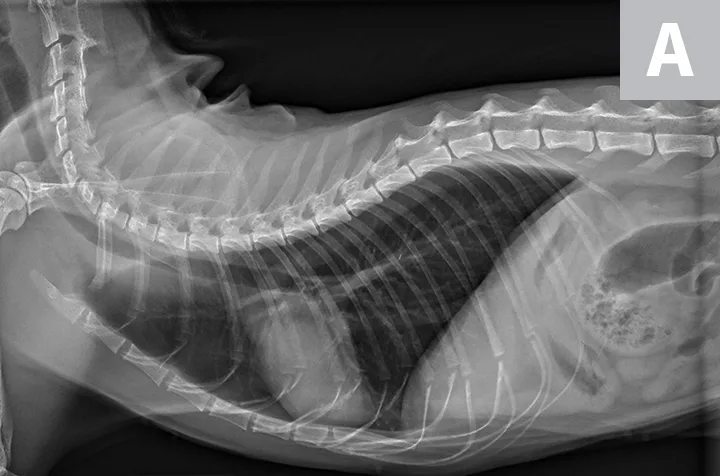

FIGURE 3A

Relative heart size difference on lateral thoracic radiographs of a normal basset hound (A) and a normal greyhound (B).

The cardiac silhouette can appear larger in small-breed dogs because the heart occupies a large amount of thoracic space; conversely, the cardiac silhouette can appear smaller in large-breed dogs (eg, greyhounds) due to the relatively larger size of the thorax (Figure 3).2